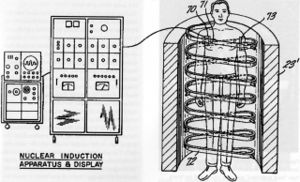

يتكون الجهاز من مغناطيس كهربائي لولبي ضخم للقيام بتشكيل مجال مغناطيسي حول المريض. هذا المجال يجعل ذرات الهايدروجين تتمغنط وتتجه جميعها إلى جزئها المغناطيسي الشمالي فتتوحد بإتجاه واحد. بعد ذالك يعرض الجسم لأشعة مذياعية تؤدي إلى زيادة طاقة هذه الذرات ولذالك سوف تغير إتجاهها بدرجة معينة وتبعث بمقدار من الطاقة عكسي . هذه الطاقة العكسية تستقبل من الجهاز وتحسب وتتكون على شكل صورة هذه الصورة توضح شدة كثافة الهيدروجين في كل منطقة من مناطق الجسم. عن طريق هذه الصورة يتمكن الأطباء اكتشاف الكثير من الأمراض.